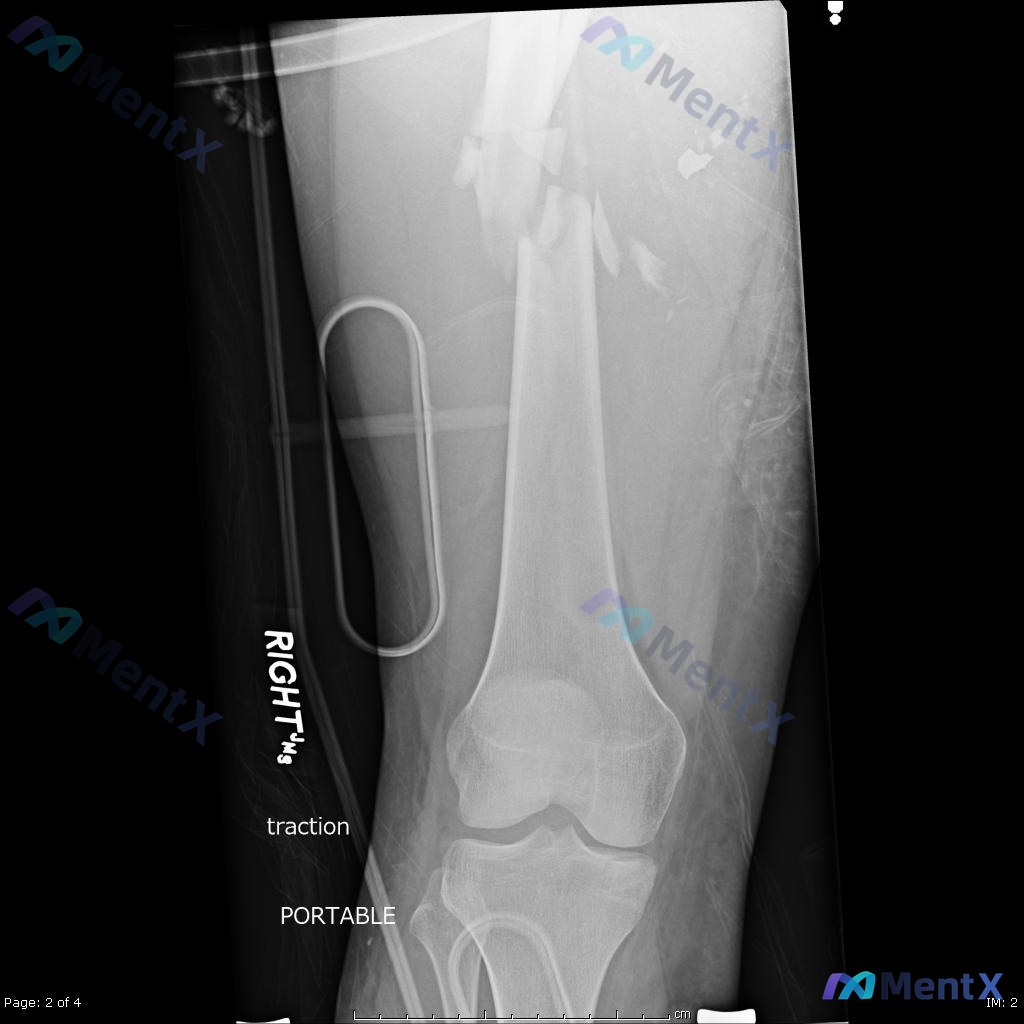

- 术前(图A/B):右侧股骨干中段粉碎性骨折,多块游离骨块,移位明显;局部软组织肿胀;髋膝关节结构未见明显异常